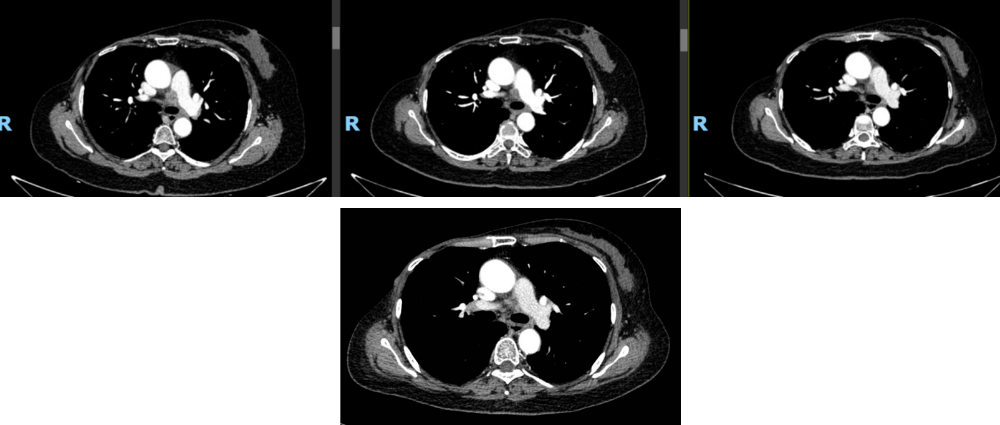

在一线阶段,患者于2023年6月接受哌柏西利联合氟维司群,并联合双膦酸盐类治疗。对于HR+/HER2-晚期乳腺癌而言,这一方案符合当下标准治疗思路。然而,至2024年6月复评时,患者出现纵隔淋巴结进展及骨转移进展,虽然肺部病灶达到PR,但总体仍判断为一线进展。这意味着患者并未获得与经典研究中相符的持久一线控制,也提示其肿瘤可能存在较强的早期耐药驱动。

治疗一周期后,影像学显示病灶明显缩小。在后续维持治疗中,靶病灶达到完全缓解(CR),非靶病灶状态为non-CR/non-PD。患者维持深度缓解状态,二线PFS高达17个月。